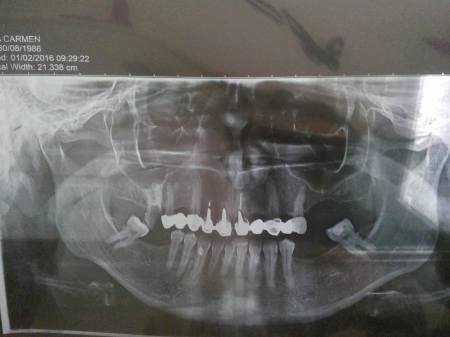

Nu am avut de ales şi m-am prezentat la doamna doctor care mi-a pus lucrarea în anul 2006 (da, încă mai profesează). După ce m-a văzut, m-a trimis să-mi fac o radiografie panoramică (poza este la sfârşitul articolului).

Dacă nu înţelegeţi vă explic eu: 9 dinţi + 2 măsele în partea de jos şi lucrarea cu 10 elemente şi un rest de măsea în partea de sus.

Măselele din partea de sus au zburat după prima sarcină. Sarcina a păpat tot calciul din organismul meu, cele mai afectate fiind măselele.

Răbdare şi nerv pentru a opta pentru tratarea lor nu am avut, aşa că am optat pentru extracţii. Nu regret, deşi acum este mult mai greu să-mi refac partea de sus.